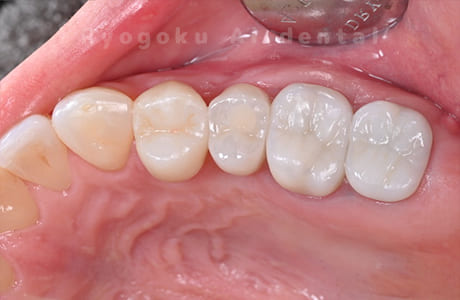

Case07

-

- 原因

- 右下6番歯根破折

- 治療内容

- インプラント治療

- 治療費用

- 約600,000円

右下の腫れが治らないとの事でご来院された患者様です。歯が割れていたため、抜歯を行い、骨に代わるお薬を入れ、インプラントを埋入致しました。経過良好で大変満足していただけました。

<リスク・副作用>

治療後、痛みや違和感、出血、腫れなどが出る事があります。喫煙者、糖尿病などの方の場合、歯が生着しない場合があります。